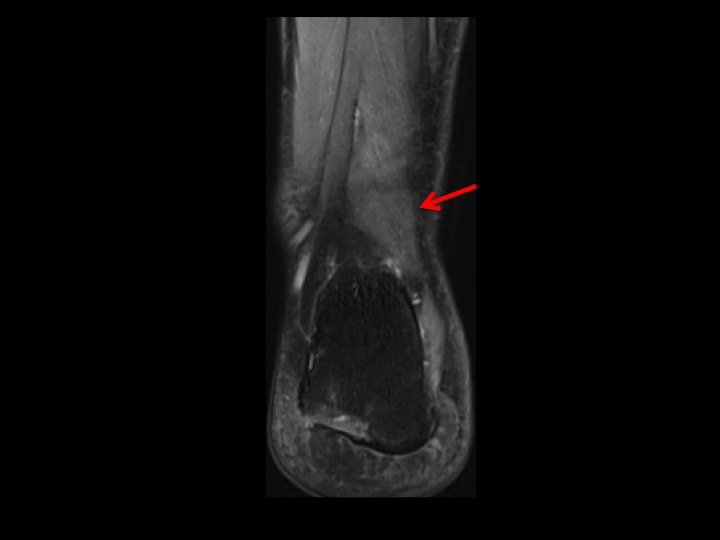

The accessory muscle in question (red arrows) appears to arise from the posterior aspect of the distal fibula. From cranial to caudal it lies lateral then posterolateral to the FHL and inserts onto the quadratus plantae. This does not conform to any of the reported accessory flexor muscles I can find. What would you call it? It shares the same insertion as the FDAL, but does not course superficial to the Posterior Tibial NV bundle. (Did you notice the peroneus quartus? She seems to have too much of everything!) Reference article.